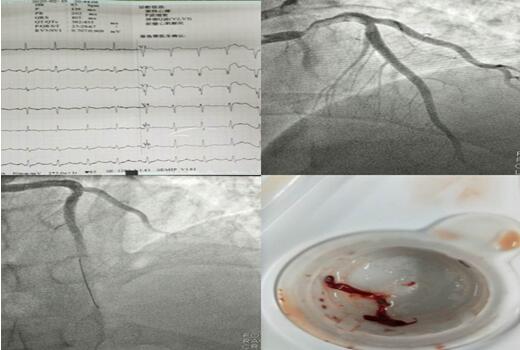

2月10日00:10,患者張某,50歲男性,突發(fā)胸痛2小時,悶痛,位于胸骨后……;

2月15日21:00,患者劉某,56歲女性,突發(fā)胸痛4小時,位于心前區(qū),呈絞榨樣疼痛……;

2月20日20:40,患者魚某,46歲男性,突發(fā)胸痛6小時,位于心前區(qū),呈絞榨樣疼痛……;

3個夜晚,3段急促的電話鈴聲打破了夜的寂靜,電話另一端傳來家屬的焦急與擔(dān)心。在接到胸痛中心電話的第一時間,3個夜晚的值班醫(yī)生立即進(jìn)行各項(xiàng)準(zhǔn)備,通知當(dāng)班護(hù)士備好讓搶救物品及藥品。患者被送達(dá)到科室同時啟動導(dǎo)管室,進(jìn)行術(shù)前相關(guān)檢查,明確手術(shù)指征、與患者家屬談話說明病情。 3個不同的夜晚,無影燈下卻站著同樣的2個人,崔旭輝主任與張洪亮醫(yī)生正在爭分奪秒的搶救患者的生命。他們?yōu)槠渲袃擅颊哌M(jìn)行了支架植入術(shù),為另一名患者抽吸出血栓。術(shù)后3名患者生命體征均平穩(wěn),癥狀較前緩解。

2月11日,患者毛某行CRT-D術(shù),該患者是一位69歲的男性,因勞力性胸悶、氣短入院,多次因心衰于當(dāng)?shù)蒯t(yī)院住院治療,因疫情影響,輾轉(zhuǎn)來到我院,入院后行冠脈造影提示正常,結(jié)合心臟超聲,診斷為擴(kuò)張型心肌病,給予強(qiáng)心、利尿、擴(kuò)冠后心衰糾正但不明顯。崔旭輝主任指出:該患者左室射血分?jǐn)?shù)降低(LVEF28%),NYHA心功能Ⅳ級,左束支傳導(dǎo)阻滯,QRS增寬大于120ms,有行CRT-D指征,即通過雙心室起搏器同步刺激左、右心室再同步化治療及埋置性心臟除顫器以改善心功能、治療惡性心律失常。術(shù)后患者QRS波群時限縮短、癥狀明顯改善?;颊叱鲈寒?dāng)天,科室收到來自患者家屬的感謝信,這份感謝信是對我們最好的禮物,是對我們工作的肯定和贊許。